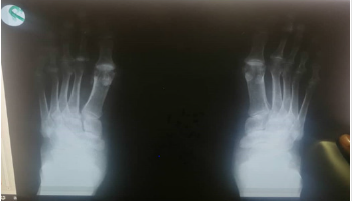

In this case, the patient was diagnosed with jaccoud’s arthritis that is most likely due to the previous recurrent attacks of rheumatic fever based on the symptoms and radiological examination of hands and foot joints. The patient’s case was further superimposed by recent rheumatoid arthritis that was evident in the high titer of rheumatoid factor, anti-CCP antibodies, CRP and ESR. The treatment was mainly supportive and methotrexate was prescribed for the rheumatoid manifestations. Further follow up is required to assess the progression of RA symptoms.